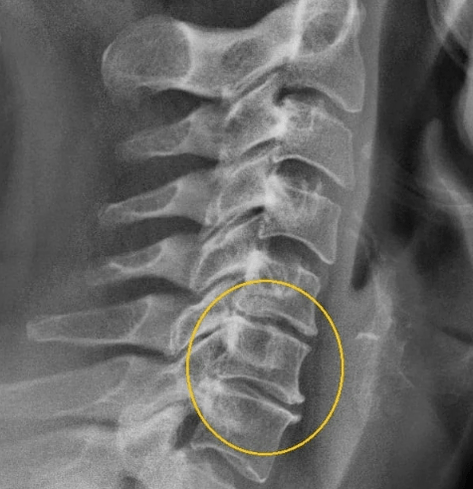

All the signs and signs of the osteocondrosis of cervical spine

Stage II

At this stage, the protrusions of the vertebrates began, intervertebral cracks were narrowed, the fiber of the collagen disk is destroyed. Due to the congestion of the result, there are symptoms of a point in strengthening the nature, neck and head loops during the movements of the heads of the head. You can already suspect the cervical osteoocondrosis here, in the second stage, the symptoms are as follows:

Stage III

The fibrous ring on the disk is destroyed, the corners occur. In the third stage, due to weak fixation, there is deformation of spine, displacement and displacement of spines due to weak fixation. Symptoms are: